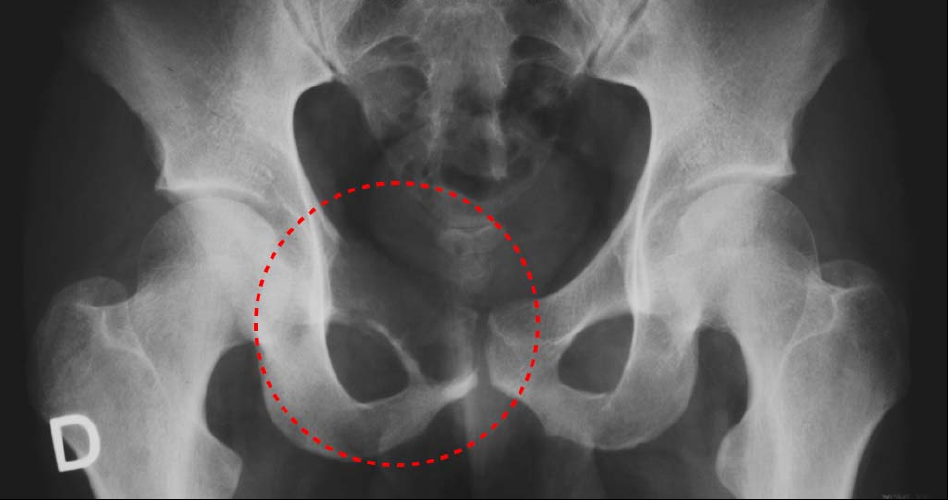

Figure4